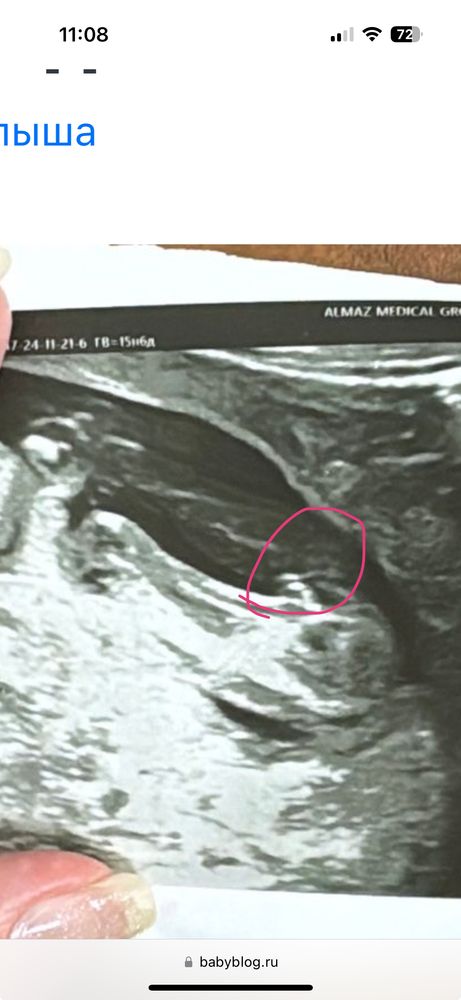

Irsik, Изображение

24.11.2024

Буду мамой, вот две половые губы , у мальчика там совсем иначе выглядит Тут совершенно точно девочка )

Буду мамой, спасибо большое, а может ли что то измениться ко второму скринингу ?)